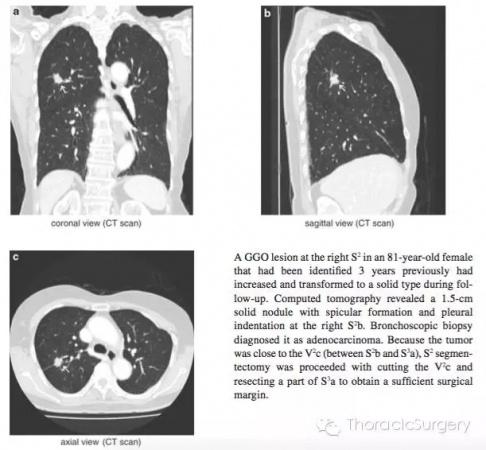

2.右侧S2肺段切除详解患者,女性,81岁,3年前发现S2段一GGO结节,随访期间发现肿瘤增大且出现实性成分。CT表现为S2b的1.5cm实性结节,伴有毛刺和胸膜凹陷征。支气管镜活检病理证实为肺腺癌。由于该肿瘤临近V2c (S2b 和 S3a之间), 遂予以S2+切除部分S3a切除,同时切断V2c,以达到足够的切缘。

图.3.2.1 通过HRCT影像从轴向,冠状面和矢状面明确肺段动脉,静脉和支气管。气管插管后通过支气管镜进一步明确B1,B2和B3分支形状和尺寸。本书中的图片是段支气管和动脉最常见的分支类型,即右上支气管分为B1和B2和B3;A1和A3段间动脉分支源于肺动脉上干。A2a是源于肺动脉上干的反支,A2b为A2的升支;段间静脉源于尖段和中央静脉。第三肋间推荐作为S2段切除的主操作孔。